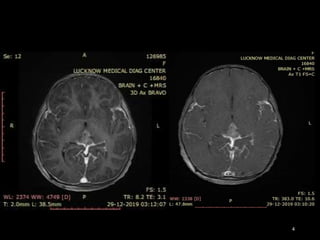

IMAGING FINDINGS

CT FINDINGS

• NECT-

Hyper dense compared to brain .

Appear to be “draped” around the posterior third ventricle.

Obstructive hydrocephalus is variable.

Pineal calcifications are “engulfed” and surrounded by tumor .

Look for a second lesion in the suprasellar region!

• CECT- Strong uniform enhancement is typical.

MR FINDINGS

• Iso- to slightly hyperintense to cortex on T1- and T2WI.

• T2* (GRE, SWI) may show “blooming” due to intratumoral

calcification.

• Enhancement is strong and usually homogeneous .

• Because of their high cellularity, germinomas may show

restricted diffusion.

CASE SUMMARY

• 9yr old female patient present with headache and

numbness of limbs

• On imaging shows Relatively well define

hetrogenous enhancing mass lesion in pineal region

and concurrent suprasellar mass with

leptomeningeal spread

• Likely Diagnosis is GERMINOMA

• HPE is awaited